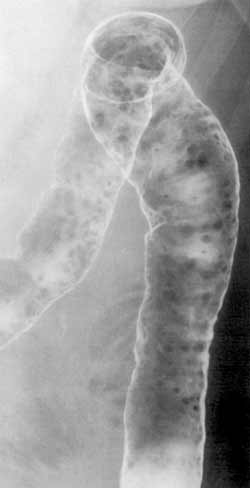

Неспецифический язвенный колит.

Рис. 7. Псевдополипы - множественные, различной величины, округлые (редко - извитые) дефекты наполнения.